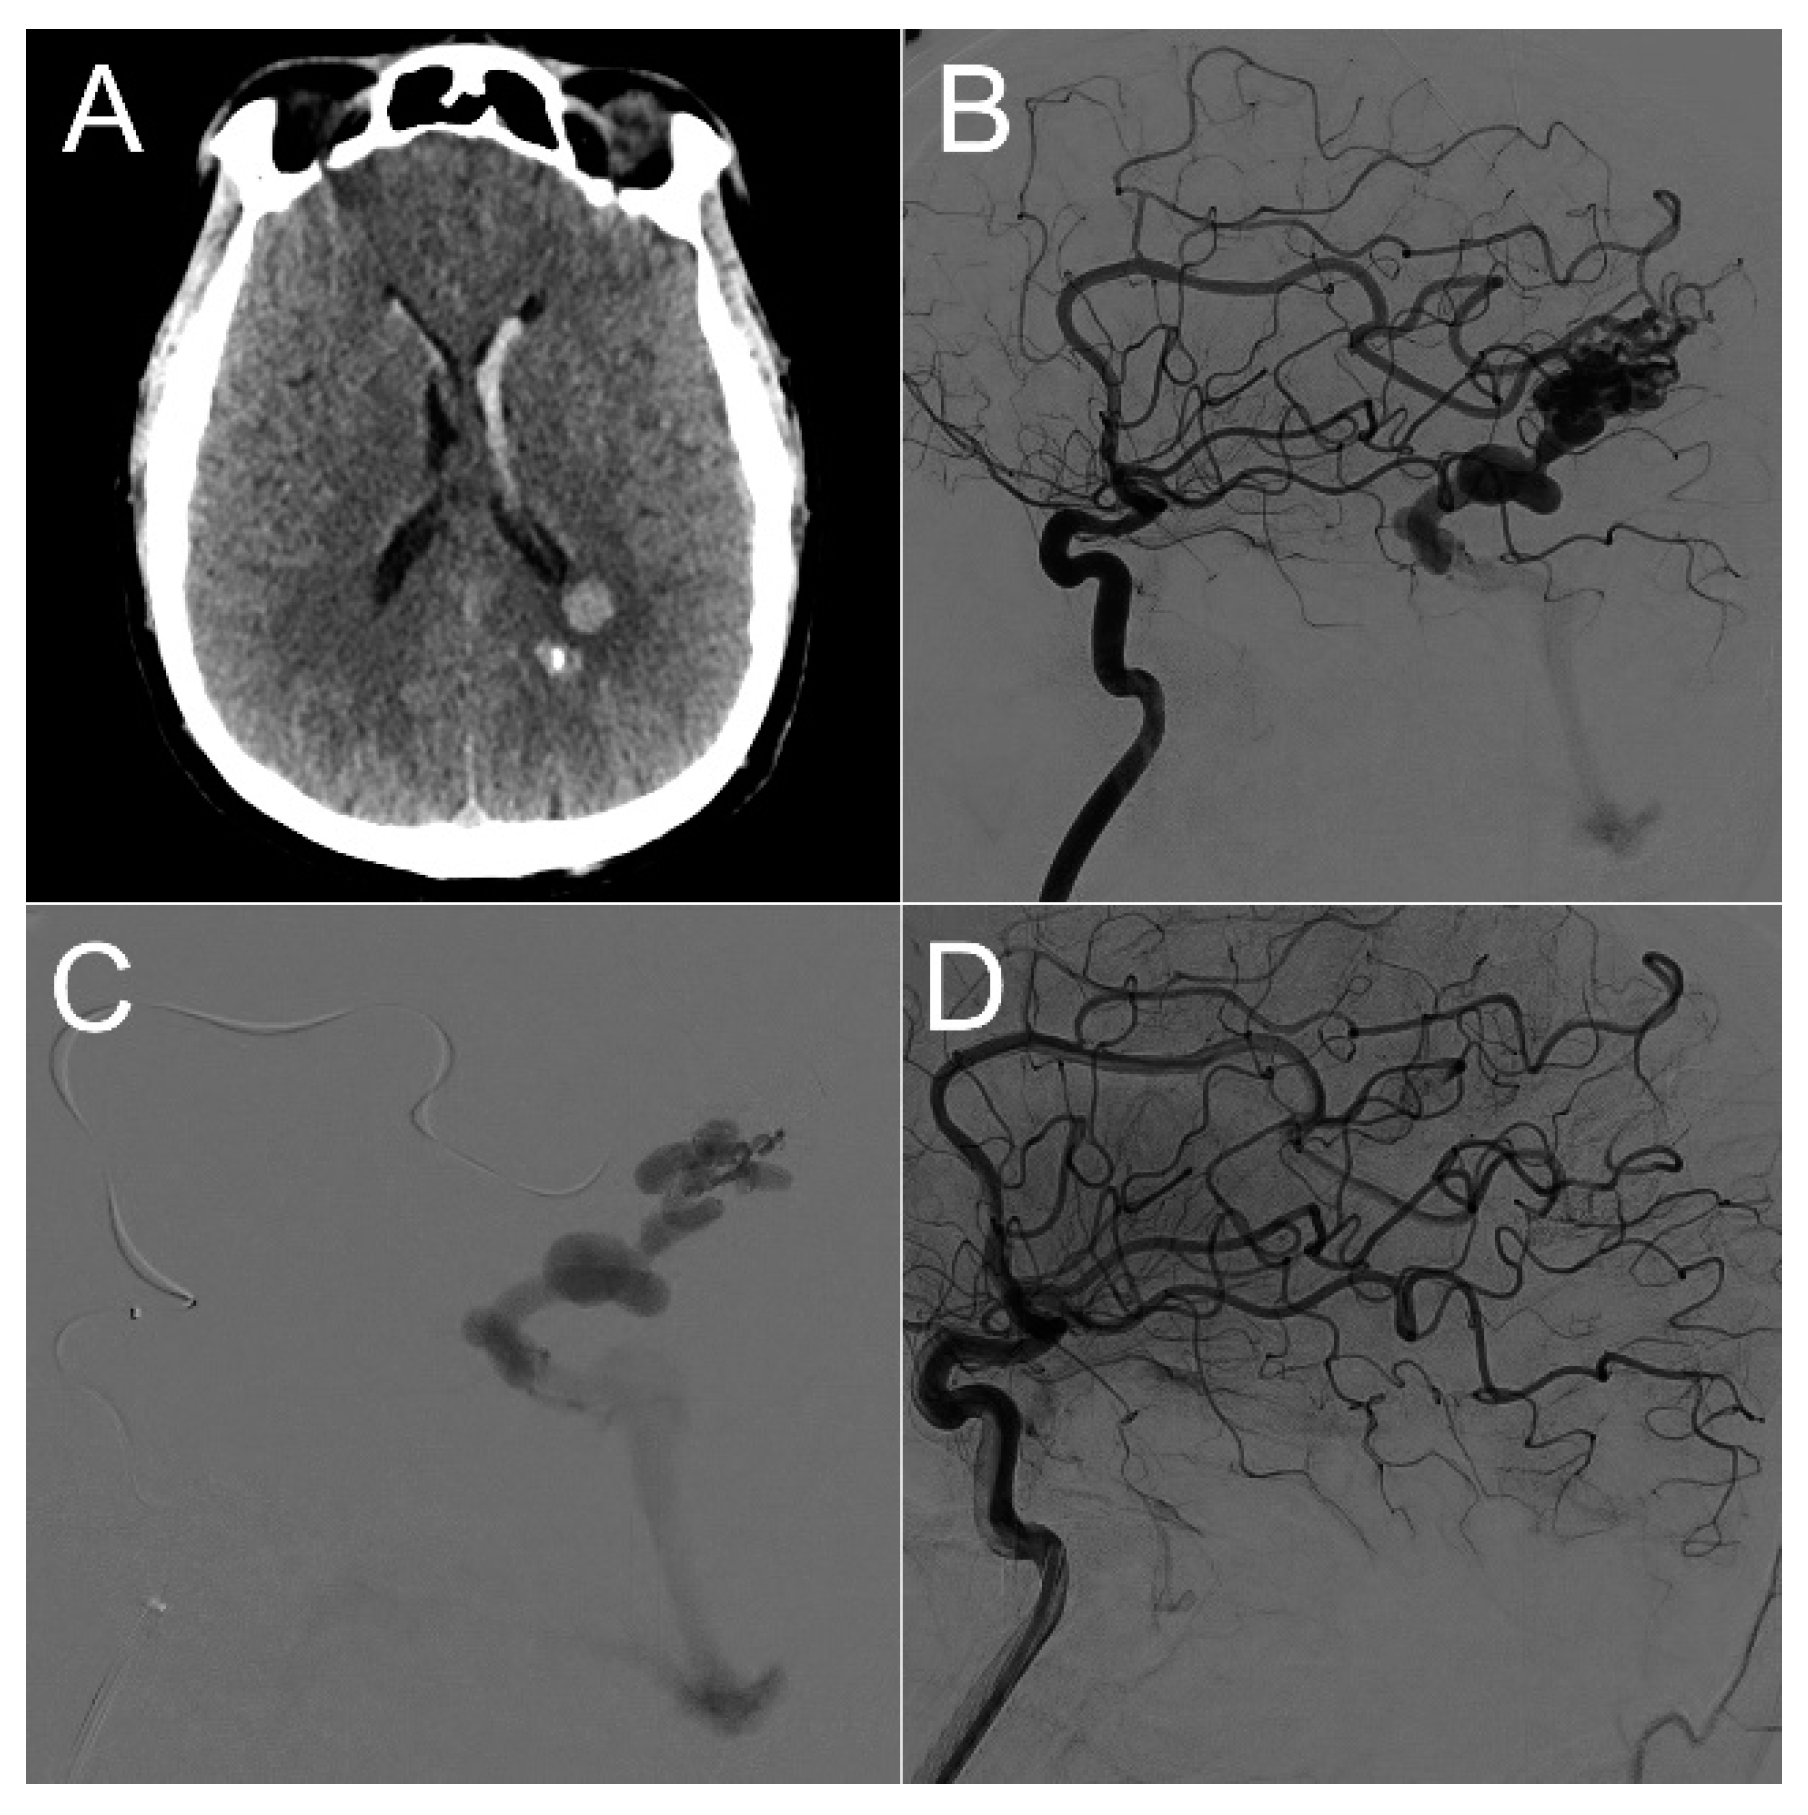

- The location of the hematoma was consistently distant from the arteriovenous malformation (AVM) nidus, surrounding the trajectory of the ventricular catheter.

- The occurrence of the hemorrhagic complication transpired several weeks after the initial AVM rupture and several days after the placement of the VPS.

- Catheter-related DICH manifested in all 10 cases without any evident coagulation disorders or other identifiable risk factors.